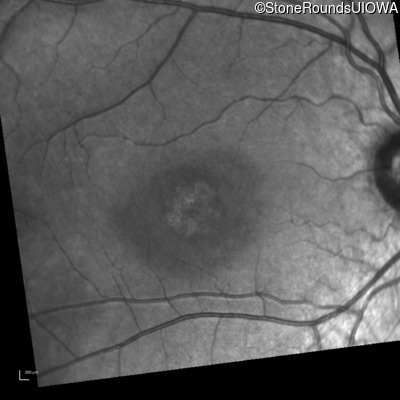

Infrared Fundus Photograph - Left - 20/200

Exemplar